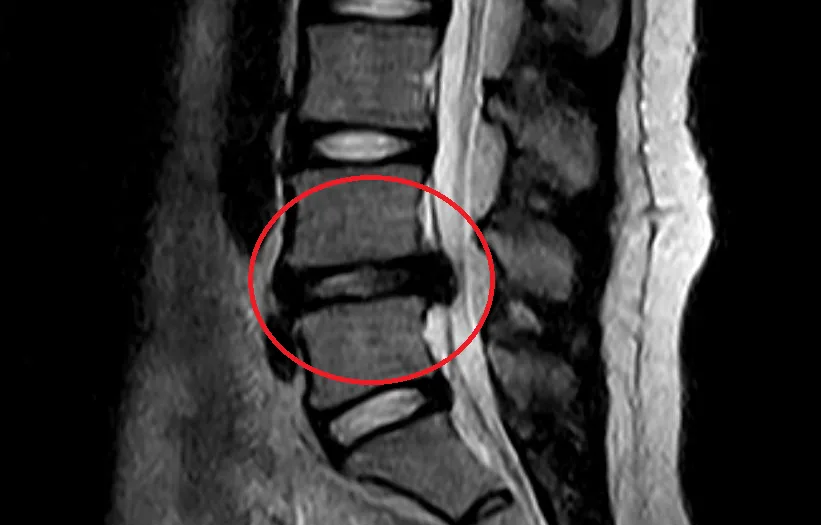

腰椎椎間板ヘルニア

Lumbar Disc Herniation